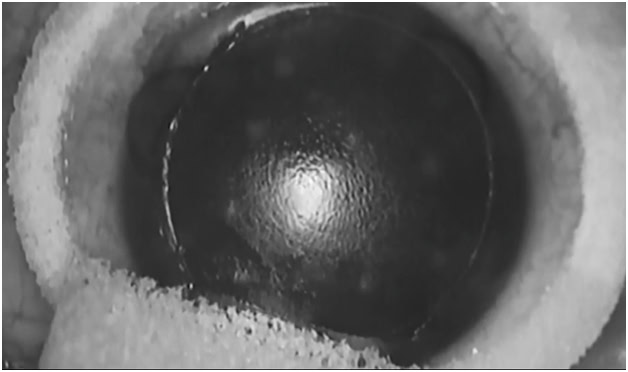

Фемтосекундният лазер значително подобрява точността на LASIK процедурата и се нарича FemtoLASIK (FLASIK), хирургичните рискове са намалени при LASIK-азначетелно, което предполага по-бързо възстановяване на роговицата и по-кратък реконвалесцентен период.

Днес в СОБАЛ „Пентаграм” използваме само най-новата платформа на фемтосекундният лазер VICTUS (Bausch+Lomb, Technolas Perfect Vision), която е и най-добрата по всичките и показатели сравнени с тези на други фемтосекундни лазери в света. Поради точността на лазерното рязане, флеповете са с правилна форма идеално центрирани и предсказуема дебелина до 1 микронв сравнение с тези, направени смикрокератом.